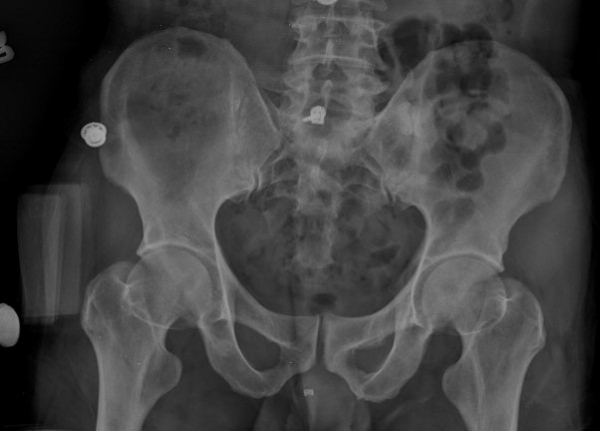

ŽÃËÀÚ¸¦ ¾ûµ¢ÀÌ °üÀý ¿ÜÃø Á¾´Ü¸é°Ë»ç ½Ã ÀüÇÏÀ屨(AIIS)¿¡¼­ ¼®È¸È­¼º À½¿µÀÌ °üÂûµÊ(»çÁø 2, 3).

´Ü¼ø¹æ»ç¼±°Ë»ç

ÃÊÁø ½Ã ½ÃÇàÇÑ ¹æ»ç¼± ÃÔ¿µ»ó ÀüÇÏÀ屨 ºÎÀ§¿¡¼­ ¼®È¸È­ À½¿µÀÌ °üÂûµÇ°í, 3ÁÖ ÈÄ ½ÃÇàÇÑ ÃÔ¿µ¿¡¼­

¼®È¸È­ À½¿µ ¼Ò½ÇÀÌ È®ÀεÊ.